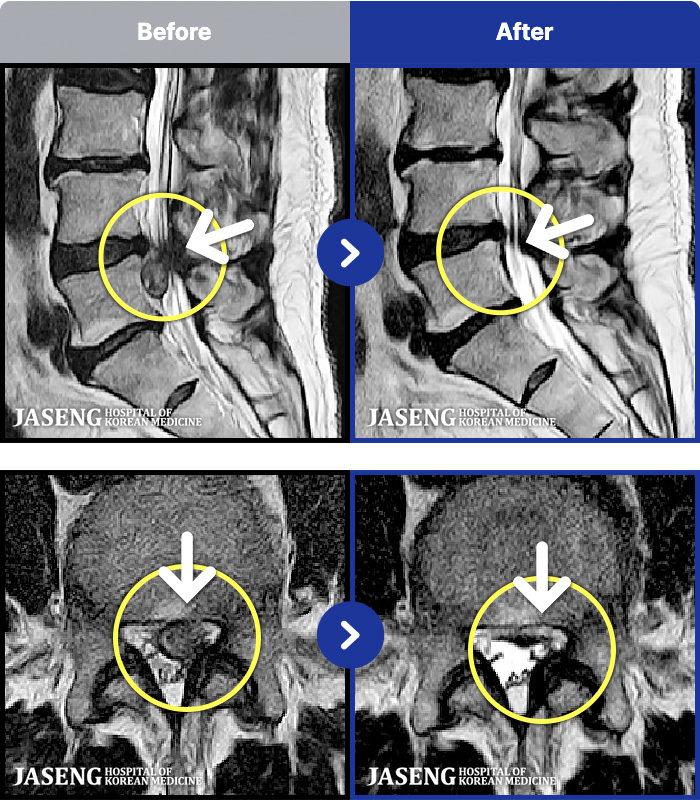

1,268 MRI ũ ʸ Ȯϼ.